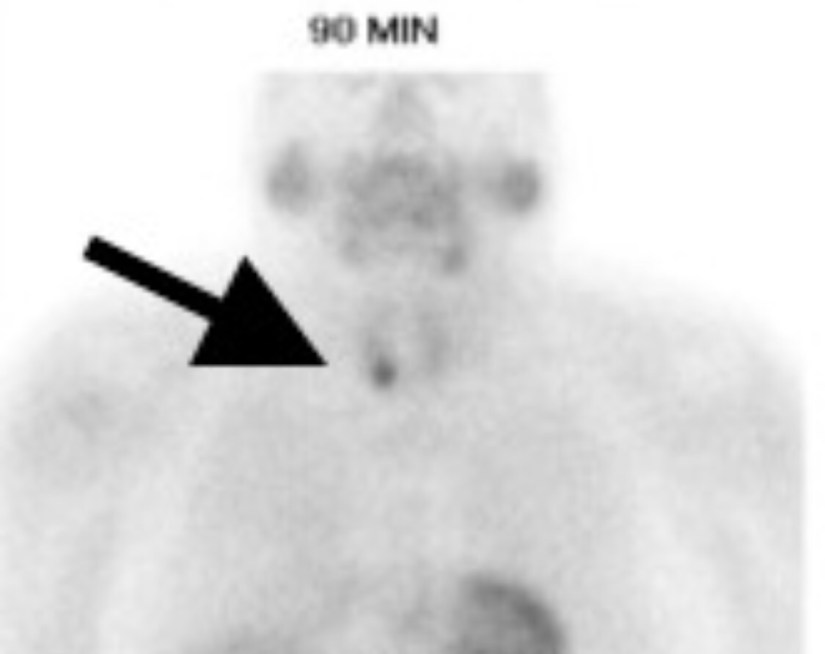

👉Los pacientes con una gammagrafía paratiroidea negativa tienen menos probabilidades de ser referidos a un cirujano (42.9# contra 72.6% para una gammagrafía positiva), aunque un estudio negativa no excluye una paratiroidectomía curativa.